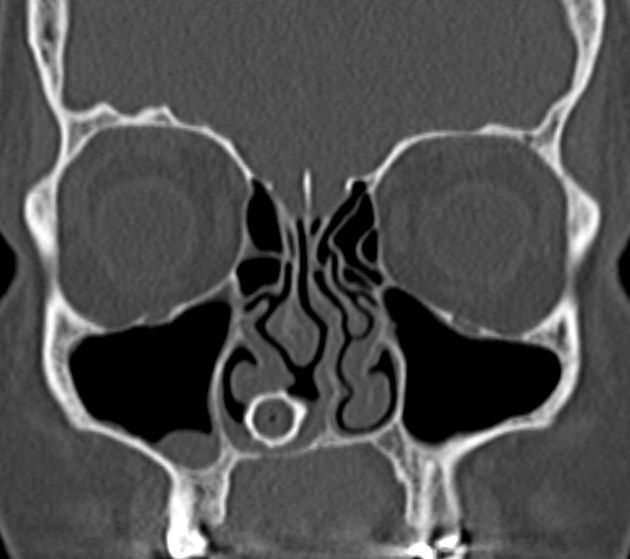

Rhinolith is a lesion that arises in the nasal cavity due to chronic inflammatory response against a lodged foreign body that results in total or partial encrustation of the particulate with minerals. This condition can present with symptoms of unilateral purulent nasal discharge and nasal obstruction that leads to medical consultation.